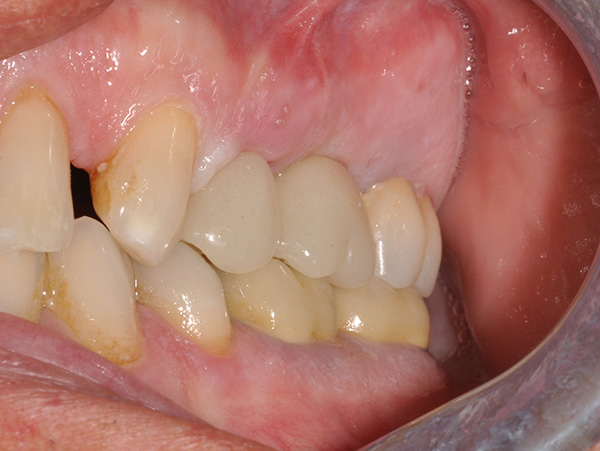

A causa della frattura della radice vestibolare del 24, tramite sondaggio puntiforme e fistola, si è proceduto alla separazione del ponte 24-x-26, conservando l’elemento 26.

L’intervento è stato eseguito dal Dr. Alessando Casolino (Bologna) dello Studio del Dr. Casolino e la protesi è a cura dell’Odt. Massimo Venerato (Lab odontotecnico C.P. Dental) su MUA tipo A dritti dell’altezza di 1 mm.